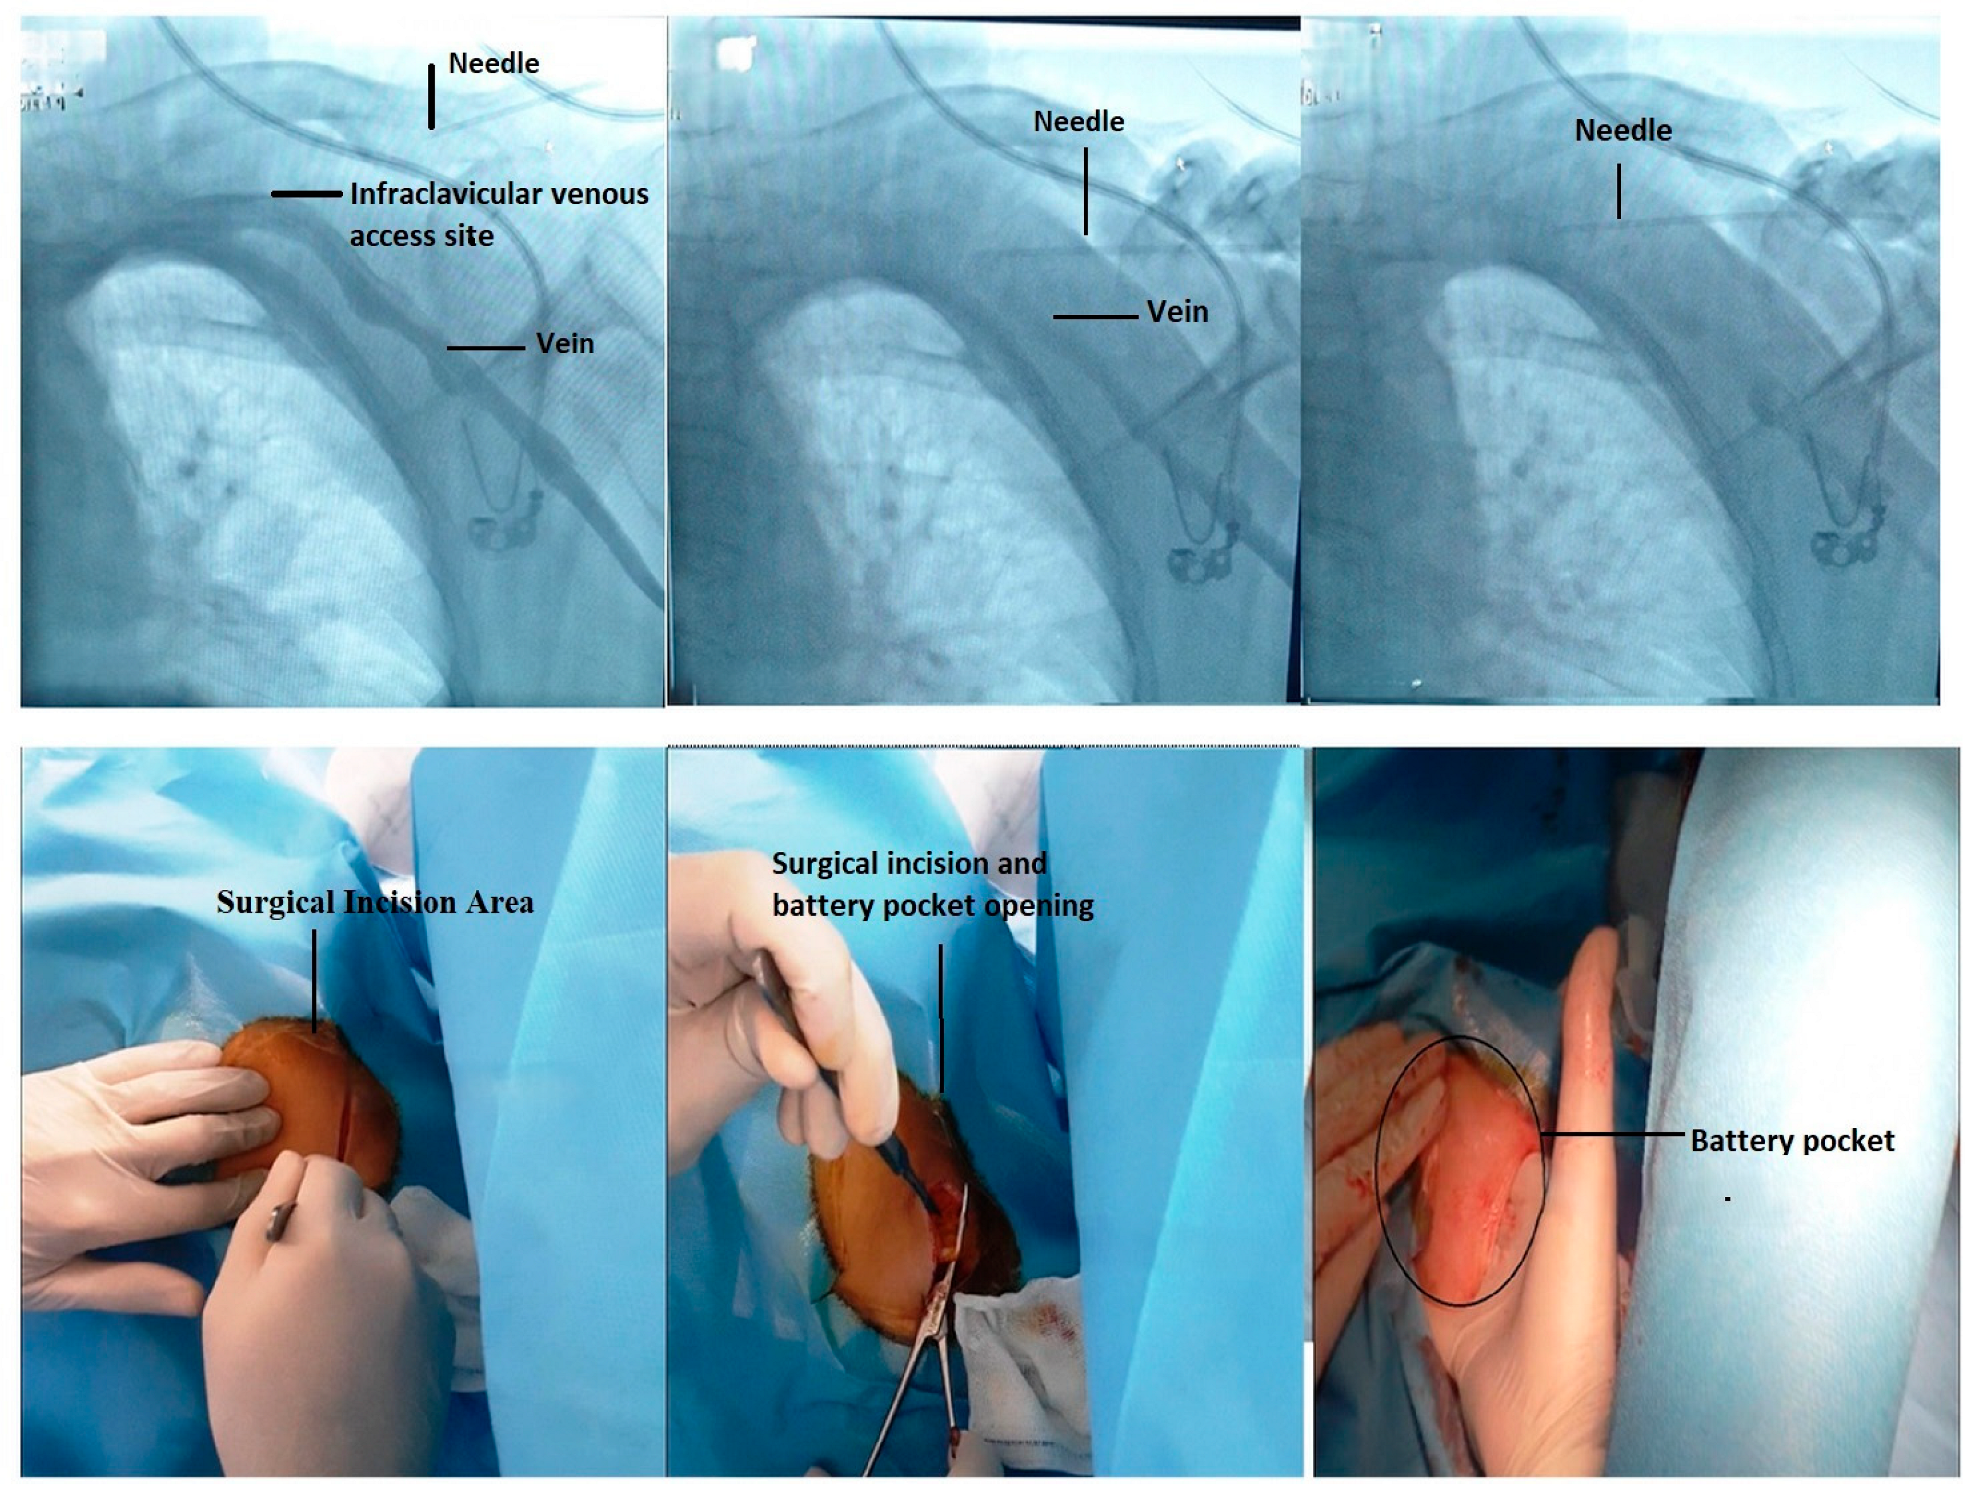

4.1. Fluoroscopic-Guided Vascular Puncture in Posterior–Anterior (PA) Projection